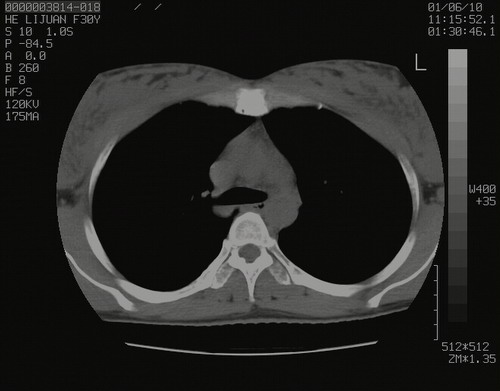

怀孕3个月时(2009-3至4月间),自述突感左侧前后胸疼痛1天,以前胸明显,随后偶感闷痛,余未见异

左肺尖脊柱旁沟肿块,境界清楚,边缘光滑,密度不均,内有多发点片状钙化,考虑良性肿瘤,骨软骨瘤或神经源性肿瘤可能,肺错构瘤不除外。

左后上纵隔见一类圆形肿块影,外侧边界清,密度不均匀,内可见点状钙化影,增强呈不均匀强化,考虑神经源性肿瘤可能。期待病理结果。